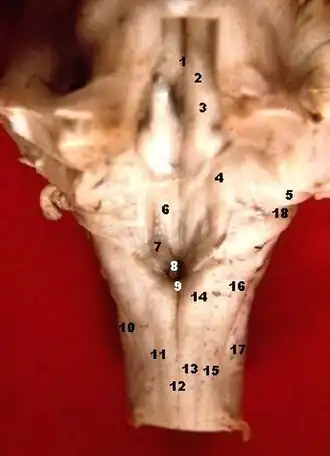

![]() Rhomboid fossa. (Area postrema labeled at bottom center.) | |

Human caudal brainstem posterior view description (Area postrema is #8) | |